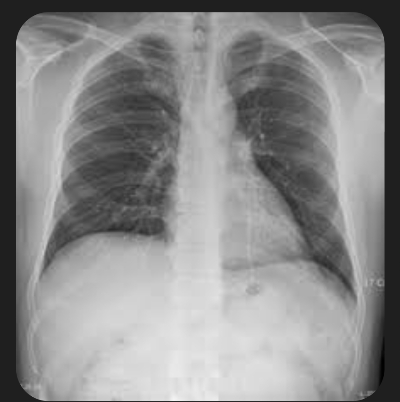

5. 폐렴 증상

폐렴 증상은 질환이 진행되면서 다양하고 심각하게 나타납니다. 주요 증상으로는 고열, 후두통, 가래를 동반한 강한 기침, 흉통, 호흡곤란, 빠른 호흡 등이 있습니다. 가래는 화농성으로 노란색이나 녹색을 띕니다.